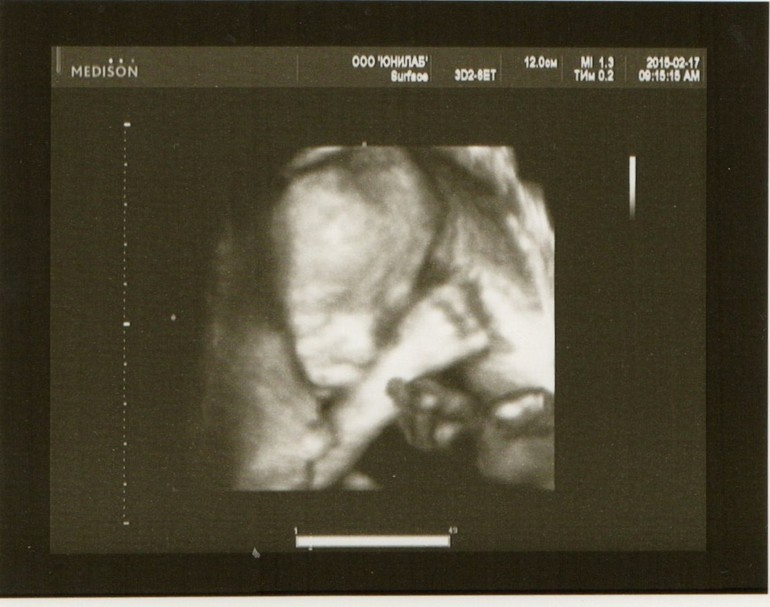

С малышкой все в порядке. Все параметры соответствуют сроку 22 недели. Предполагаемая масса плода 427г. Окружность головы 180мм. Плацента по передней стенке, больше слева, на 79мм выше внутреннего зева. Никаких патологий и отклонений не обнаружено. Отдельно озвучили, что нет "волчьей пасти" и "заячьей губы". Сначала Наталья Юрьевна не смогла увидеть пол, т.к. малыш лежал в неудобном положении, еще и прижав обе ручки к лицу. Оставили это дело на потом, под конец детка начала дрыгаться и поменяла положение. И Н.Ю. говорит вдруг: "Я вам не говорила, что у вас девочка?" Отвечаю: "Предположили в 12 недель." Н.Ю.: "А теперь 500% говорю вам - девочка!" Аааааа, как здорово!!!! Но, блин, сидит красавица наша на попе(тазовое предлежание). Конечно, времени еще вагон, надеюсь, перевернется правильно. Наталья Юрьевна очень подробно все рассказала-показала, даже в включала несколько раз режим 4D. Это что-то! Так здорово было видеть объемную картинку, личико нашей доченьки... Сделали несколько снимков, самые удачные нам распечатали. Мы такие радостные вышли из медцентра, не описать, учитывая, как сильно я волновалась перед узи... Боялась, что что-нибудь не так будет.

P.S. Смотрела раньше чужие 4D-фото, думала "что-то какие-то страшненькие", а теперь смотрю, милота да и только)))))